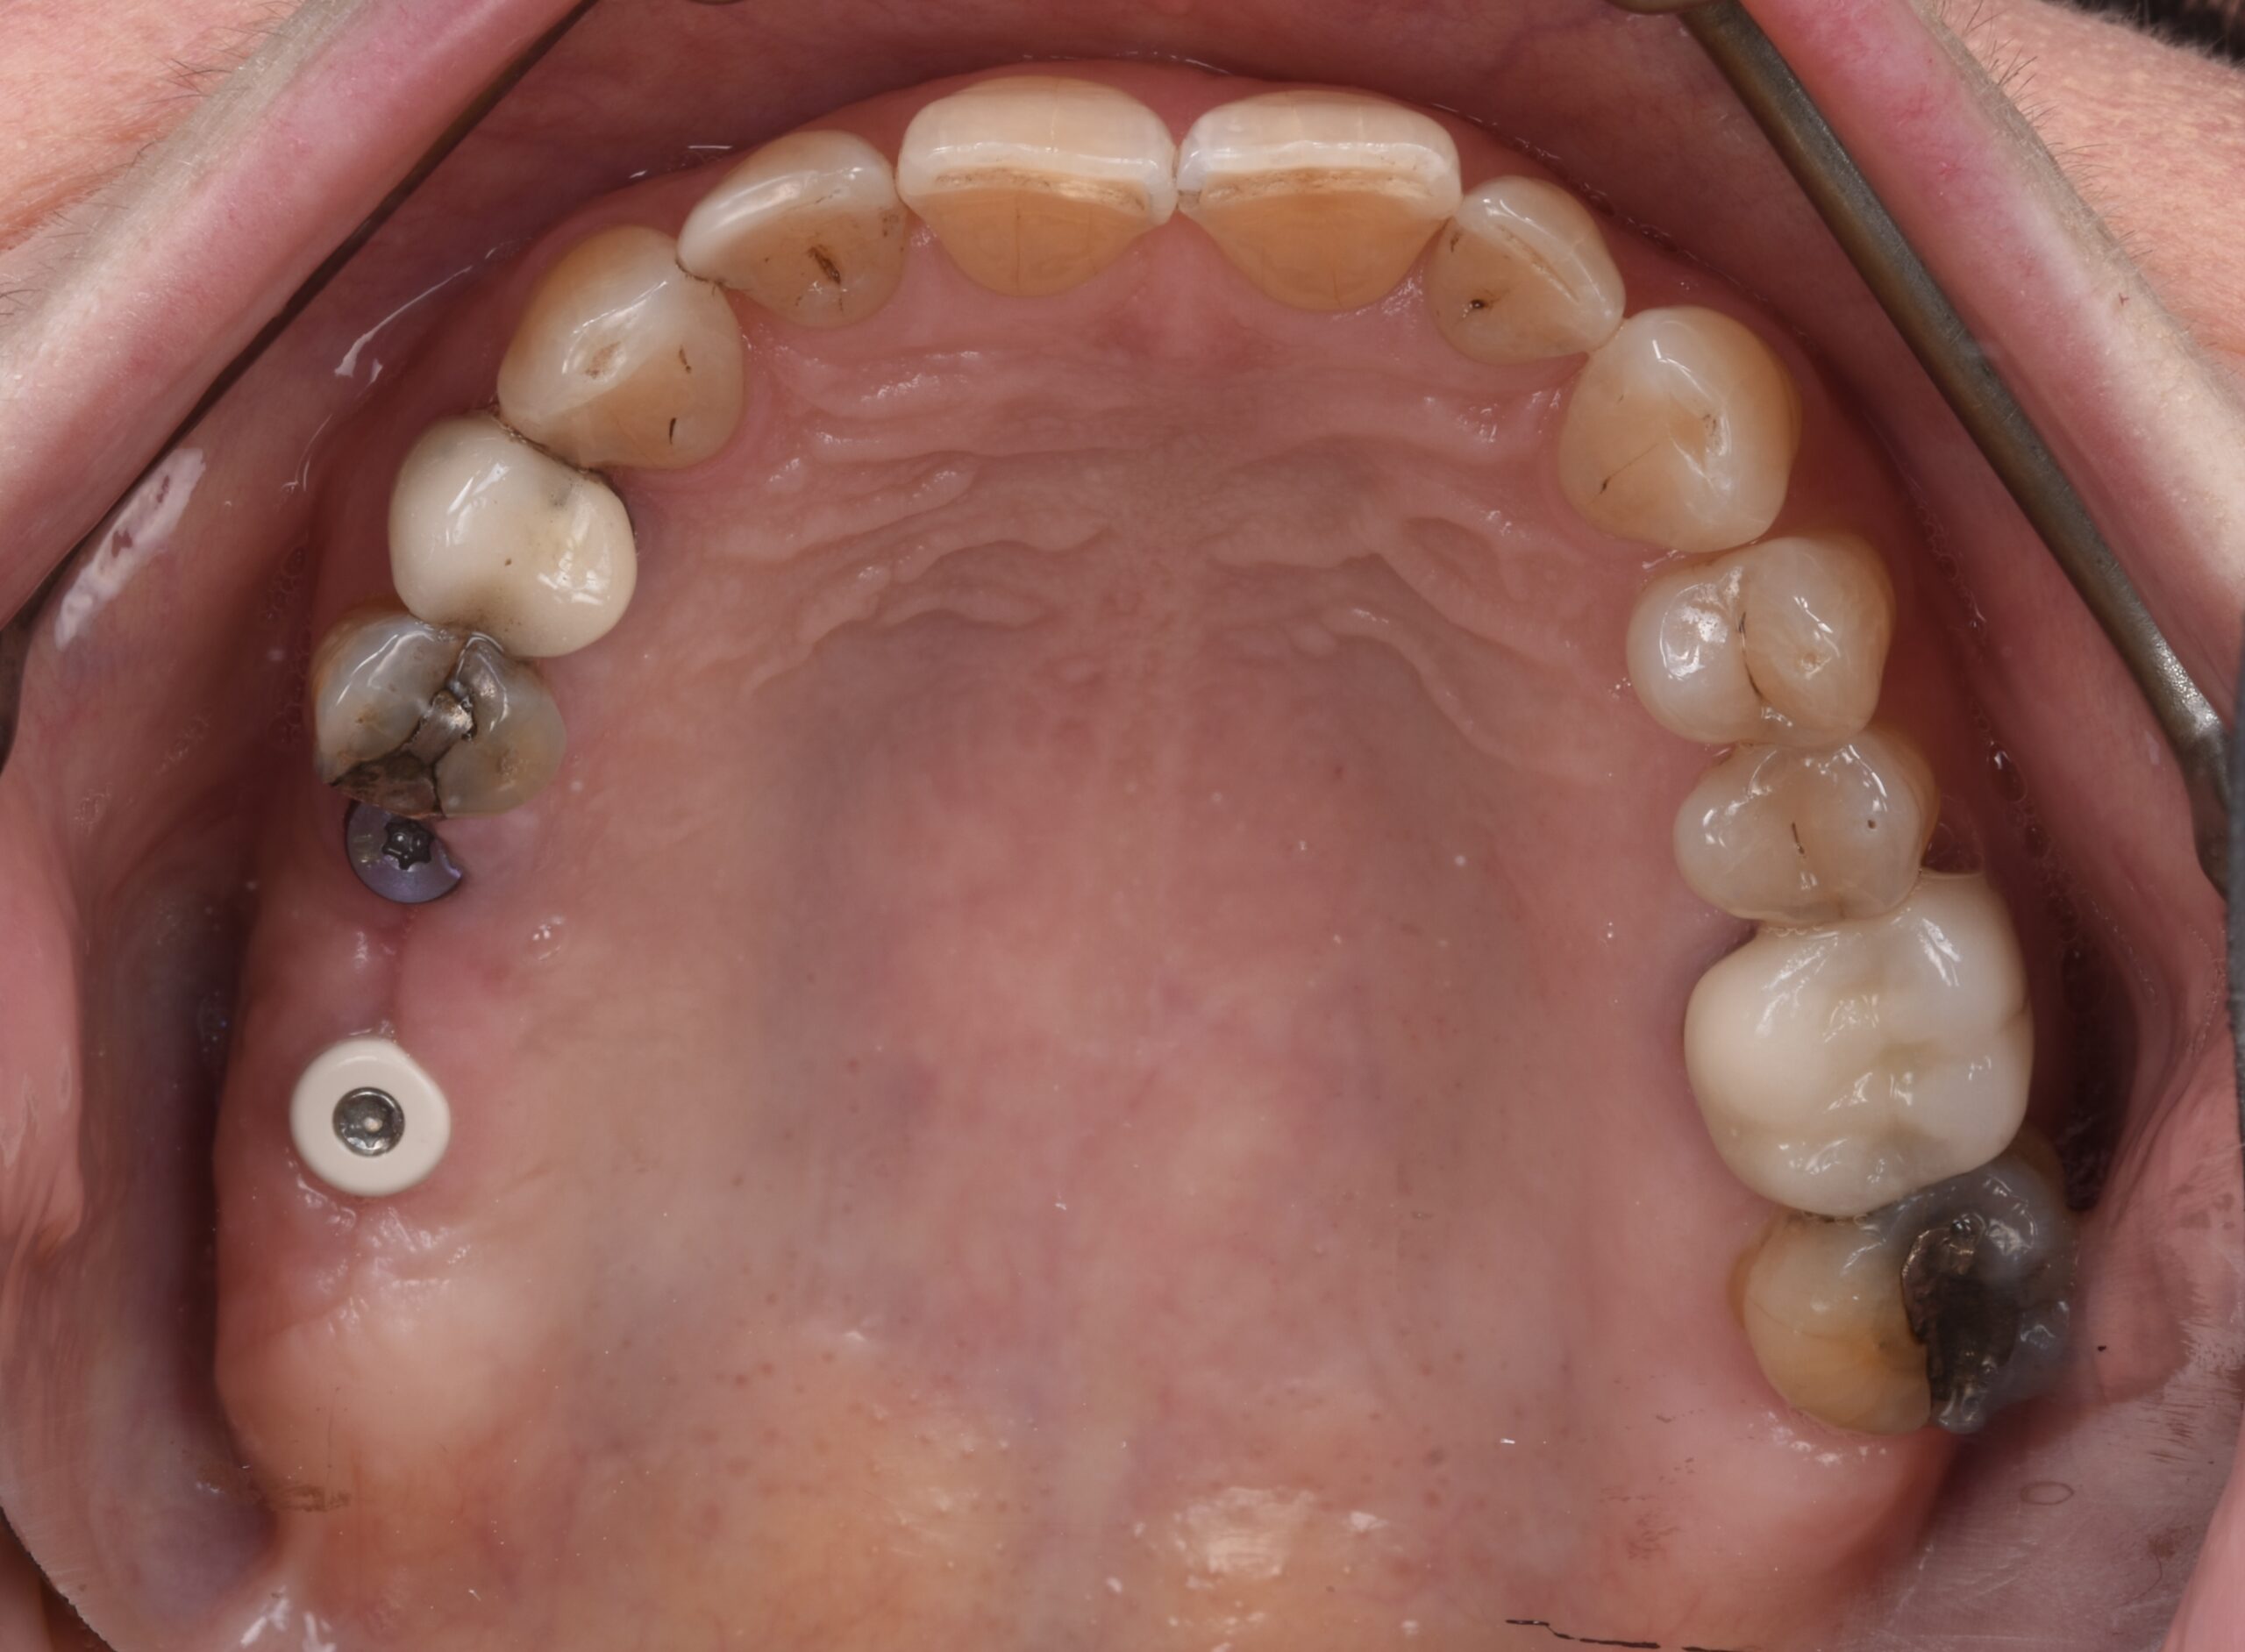

インプラントは「人工歯根」「連結部品」「被せ物」から成る構造です。人工歯根とは顎骨に埋め込むチタン製の支柱を指します。

しかし長期安定を決めるのは構造ではなく、次の三要素です。

・骨の厚みと質

1年目の骨吸収が1.5mm以内、その後は年間0.2mm以内が一つの目安です。

・角化歯肉の幅

角化歯肉とは炎症に強い硬い歯ぐきの部分です。2mm未満はリスクが上がる傾向があります。

・咬合設計

臼歯部では咬合力は体重の2〜3倍に達します。60kgの方では最大180kg相当の力が加わります。そのため咬合接触は天然歯より約0.1mm低く設計することがあります。

インプラントを希望される患者様の多くは奥歯の欠損です。奥歯は審美よりも力学設計が重要です。この力学を体系的に学ぶのが補綴専門教育です。